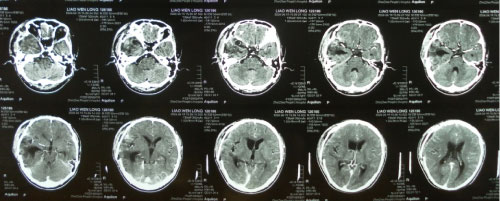

The imaging features of HPCs and meningiomas are very similar and it is difficult to distinguish them. Whether the skull has been thickened or infiltrated can be identified by the skull plain film. The CT scanning of HPCs show the slightly high-density, more clear boundary and lobulated lesions with coherences significantly (Figure 1). The adjacent skull is always accompanied with the osteolysis destruction in HPC caused by their aggressive growth characteristics, while often with appear adjacent skull proliferation in meningioma. The calcification is rarely seen in hemangiopericytoma. Therefore, it can be distinguished with HPCs from meningiomas by the osteolysis or proliferation and calcification of the adjacent skull [16].

Figure 1: The cranial CT test of HPC. View Figure 1